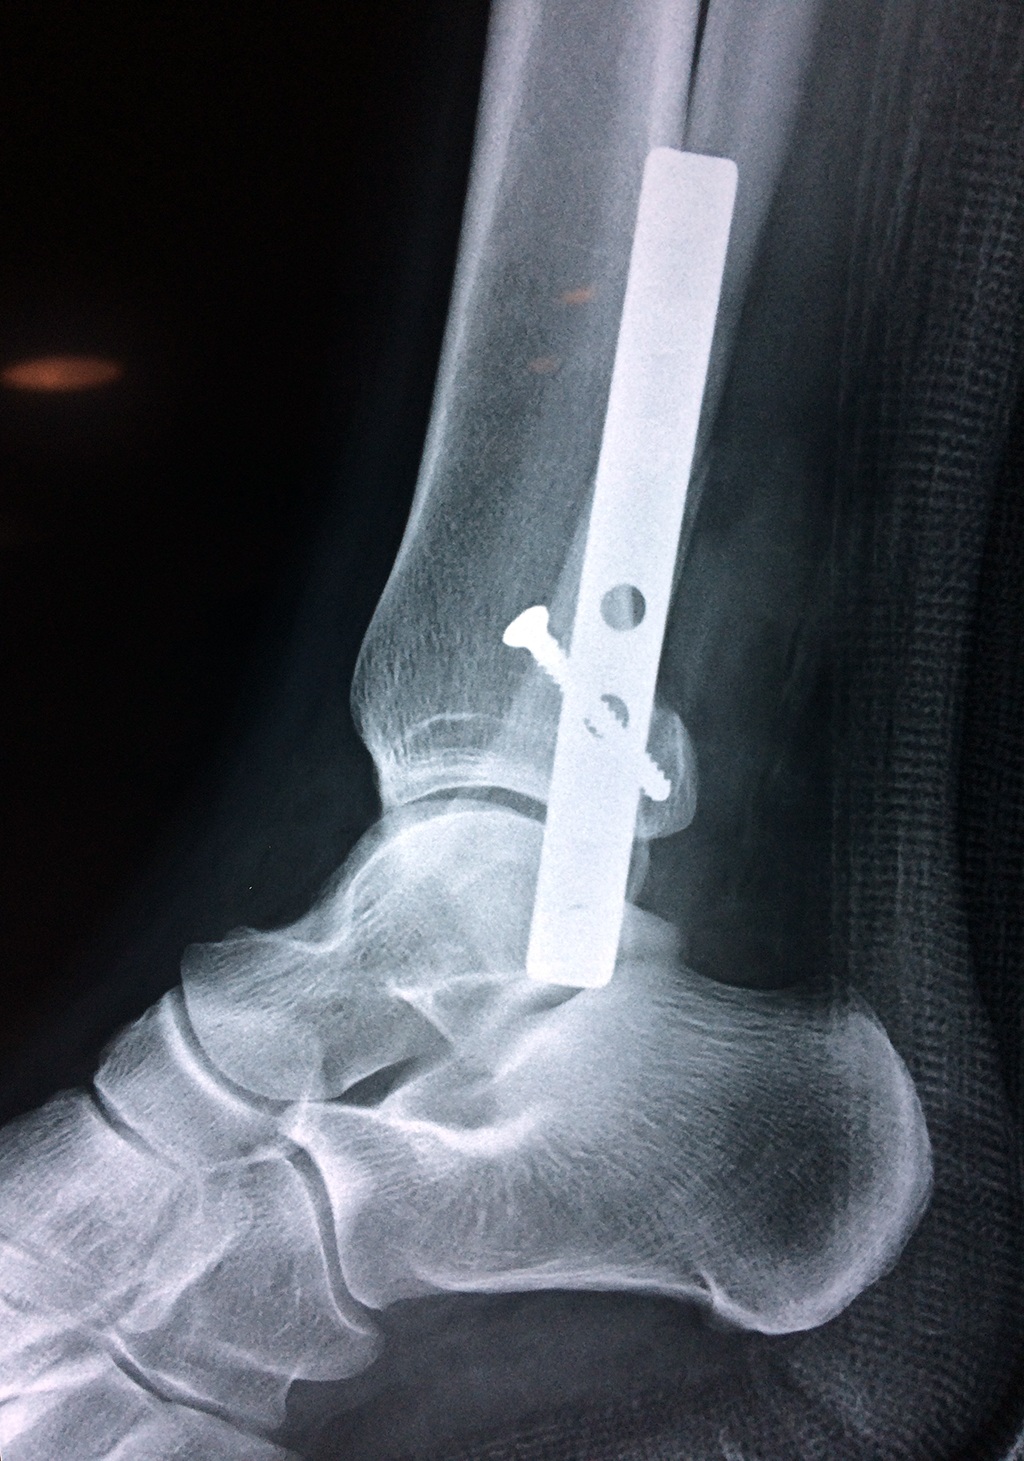

Cuando se necesita cirugía, es probable que esta implique el uso de clavijas de metal, tornillos o placas para sostener los huesos en su lugar mientras la fractura se consolida. Los elementos de soporte pueden ser temporales o permanentes.

Algunas fracturas de tobillo pueden requerir cirugía si:

- Los extremos de los huesos están desalineados entre sí (desplazados).